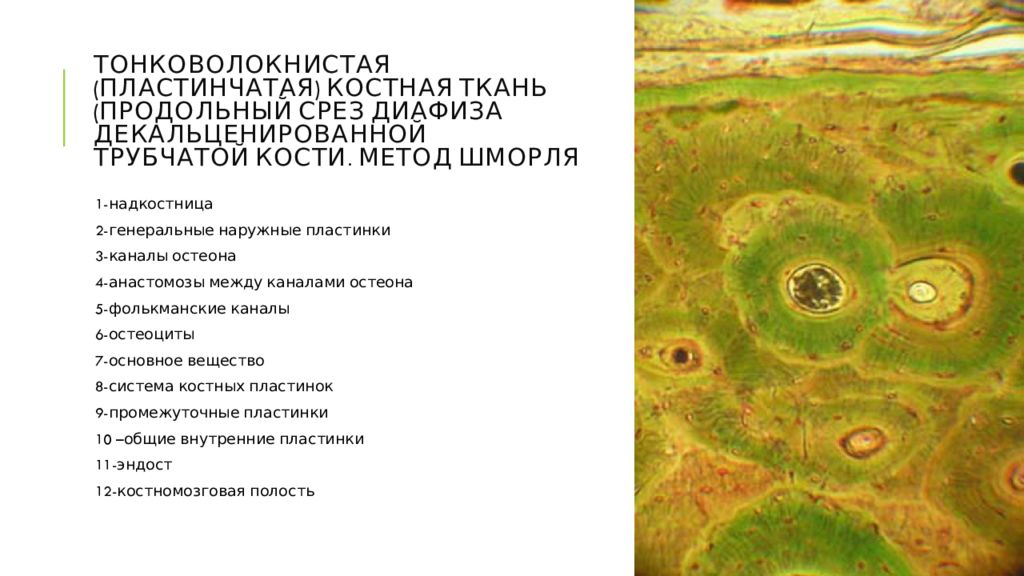

Структура грубоволокнистой костной ткани: наглядные примеры